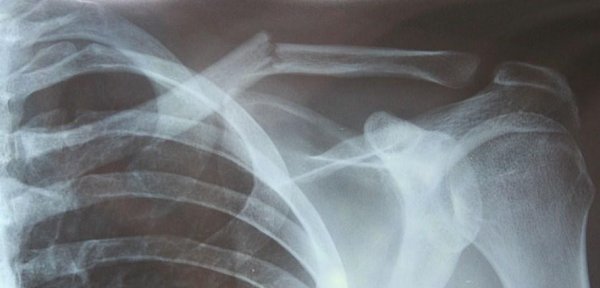

Sur cette radio, quel diagnostic? Quel est le déplacement des fragments?

Fracture de la clavicule au niveau du tiers moyen

déplacement du fragment interne en haut et arrière, du fragment externe en bas